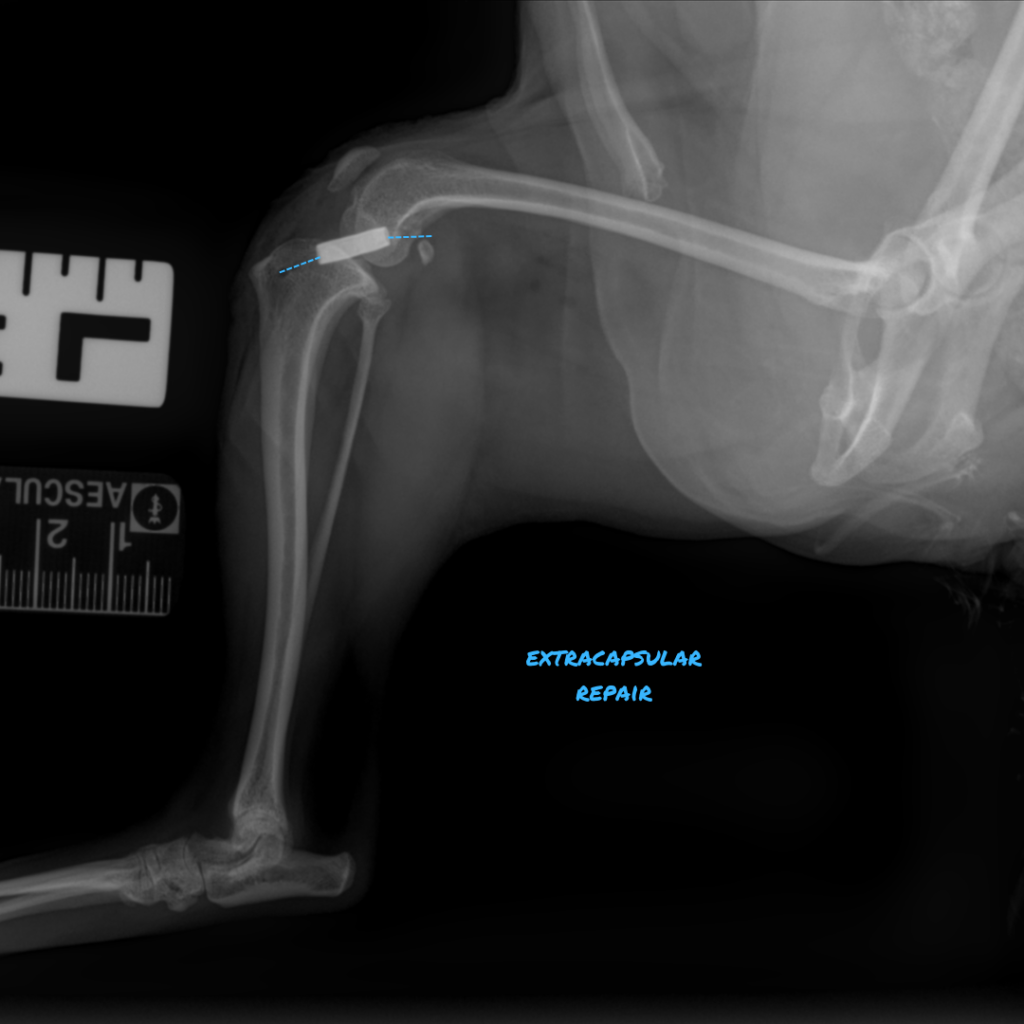

The Extracapsular Lateral Suture Technique uses a synthetic, monofilament or braided polyethylene material to address cranial tibial subluxation (Blue dotted line). However, these extracapsular sutures are not designed for permanent stabilization, as they eventually fail over time. The objective is for the suture to remain functional for 8-12 weeks, facilitating the development of periarticular scarring and allowing for sufficient muscular rehabilitation to stabilize the joint.